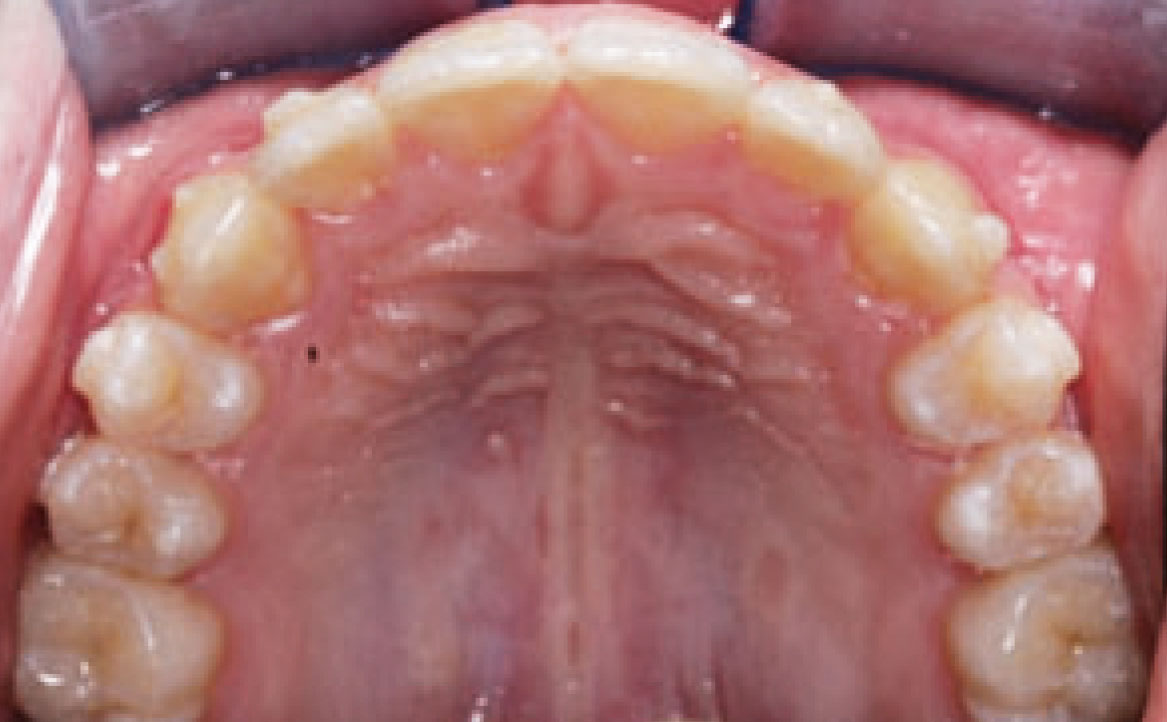

Dall’esame obiettivo intra orale si osservava una seconda classe canina destra e sinistra, una seconda classe molare destra e sinistra, e un diametro inter-canino e inter-molare ridotto sia in riferimento al mascellare superiore sia al mascellare inferiore (fig. 3A-3E).

A seguito del trattamento è stato osservato un miglioramento dell’igiene orale (fig. 5).